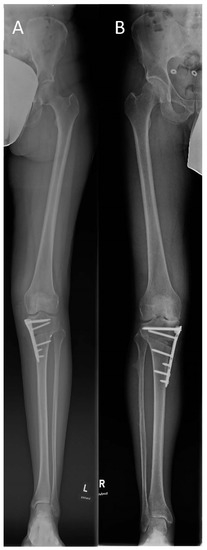

2.2. Surgical Technique

| Mechanical axis deviation in mm (preoperative) | 18.5 ± 6.9 | 21.7 ± 10.0 | 20.1 ± 8.7 | 0.151 |

| Mechanical axis deviation in mm (postoperative) | −8.0 ± 4.3 | −7.7 ± 6.7 | −7.8 ± 5.6 | 0.820 |

| Hip–knee–ankle angle in degree (preoperative) | 5.0 ± 1.7 | 6.1 ± 2.4 | 5.6 ± 2.2 | 0.057 |

| Hip–knee–ankle angle in degree (postoperative) | −2.4 ± 1.2 | −2.5 ± 1.7 | −2.4 ± 1.4 | 0.765 |